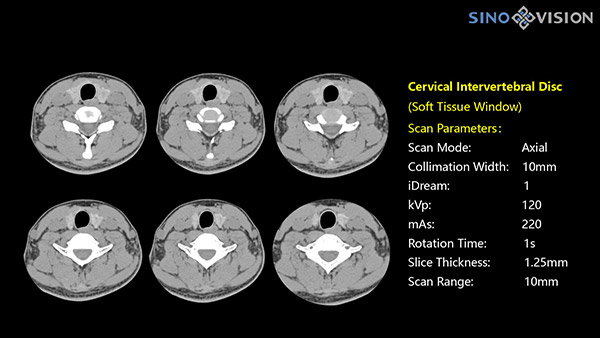

Компьютерные томографы SinoVision обеспечивают удобное размещение пациентов, превосходную визуализацию структур, включая мелкие сосуды, и низкую лучевую нагрузку.

128-срезовый КТ SinoVision InsitumCT 568 – компьютерный томограф для общих клинических исследований

Подходит для большинства рутинных и углубленных специализированных исследований, в том числе педиатрических и кардиологических исследованиях при сверхнизких дозах.